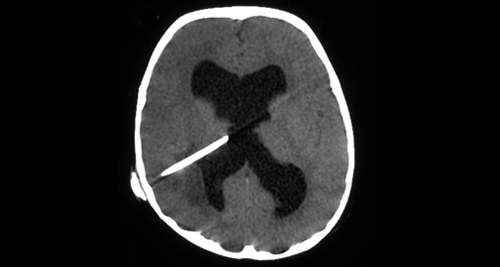

- CT scan with contrast: This is often the first diagnostic tool used. It helps locate the abscess and assess its size and position.

- MRI: Offers better detail than CT, especially in early stages or when abscesses are small or near sensitive brain structures.

In some cases, a neurosurgeon may aspirate the abscess using a fine needle guided by CT or MRI. Lab technicians analyse this sample to identify the exact bacteria, fungi, or parasite causing the infection.